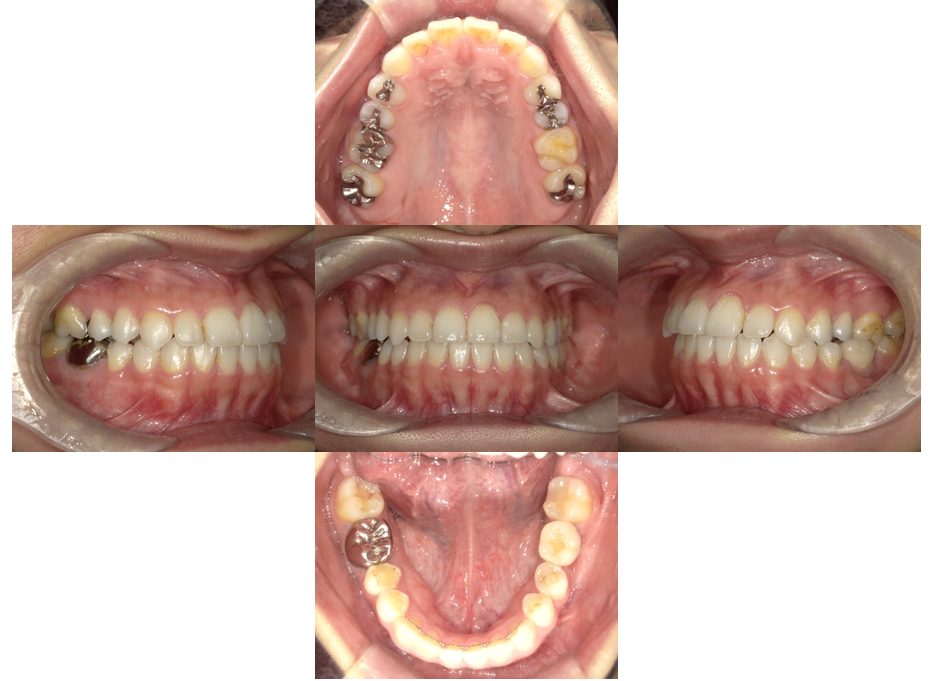

矯正治療・根管治療・補綴治療の症例紹介(三隅歯科クリニック)

三隅 賢祐(三隅歯科クリニック)

症例詳細

| 主訴 | 過去作成した右下の被せ物がずれて入っており、たまに腫れる。歯並びも気になる。 |

| 治療内容 | 矯正治療を行いました。 |

| 治療費 | 800,000円(税込み) |

| 治療期間 | 2年半(矯正治療期間 2年) |

| 治療回数 | 30回 |

| 想定されたリスク | 術前に基礎資料を整え分析し、セットアップモデル等でシミュレーションをしておかないと、予定通りの治療が行えないリスクがあった。 |